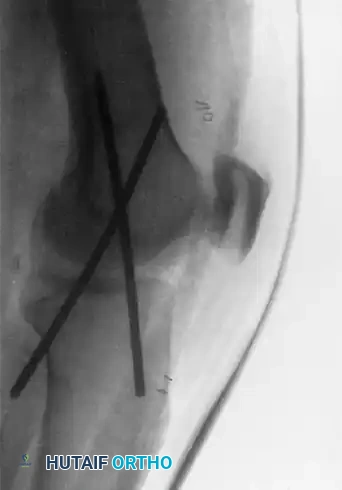

The following radiographs demonstrate the successful application of transarticular pins for temporary extraarticular fixation during the repair of torn lateral ligaments.

Figure 60-5: Radiographs demonstrating transarticular pins. (A) Anteroposterior view and (B) Lateral view illustrating the temporary extraarticular fixation with Kirschner wires utilized during the repair of torn ligaments.